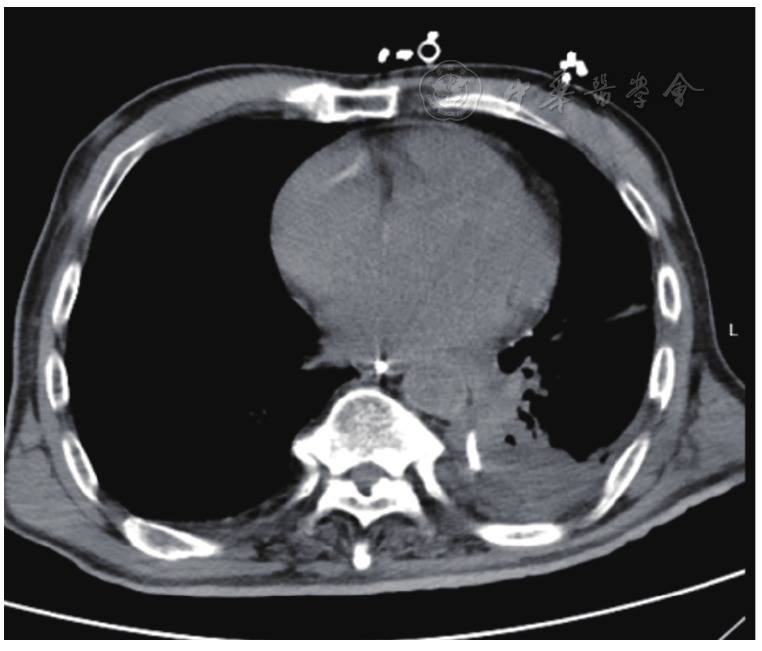

图4 术中脓胸脓壁剥离后游离到食管瘘口处,胸腔镜引导食管镜经口入胸腔,放置空肠营养管用于冲洗和引流